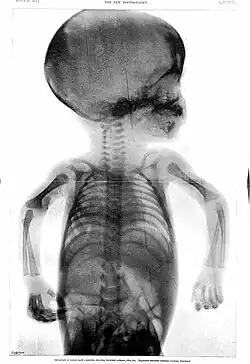

Skiagraph of three-month-old infant by Rowland, 1896

Rowland's career began in medical journalism while he was still a medical student when, in 1896, as Hart's intern, the year following the discovery of X-rays,[6] the BMJ appointed Rowland as "Special Commissioner" to produce a report on the clinical use of X-rays titled "Report on the Application of the New Photography in Medicine and Surgery."[3][6][a] It was published in 17 parts between 8 February 1896 and 12 June 1897.[3] In May 1896, he founded the world's first X-ray journal, the Archives of Clinical Skiagraph, a radiology journal that preceded the British Journal of Radiology.[3][6] In the preface to the first issue, written in April 1896, he wrote that "the object of this publication is to put on record in permanent form some sort of the most striking applications of the new photography to the needs of medicine and surgery".[6] He coined the term "skiagraphy" to describe the making of X-ray pictures and wrote some of the early works on radiology.[3] Without any radiology experts or X-ray departments at the time, his journal became an essential reading.[6]